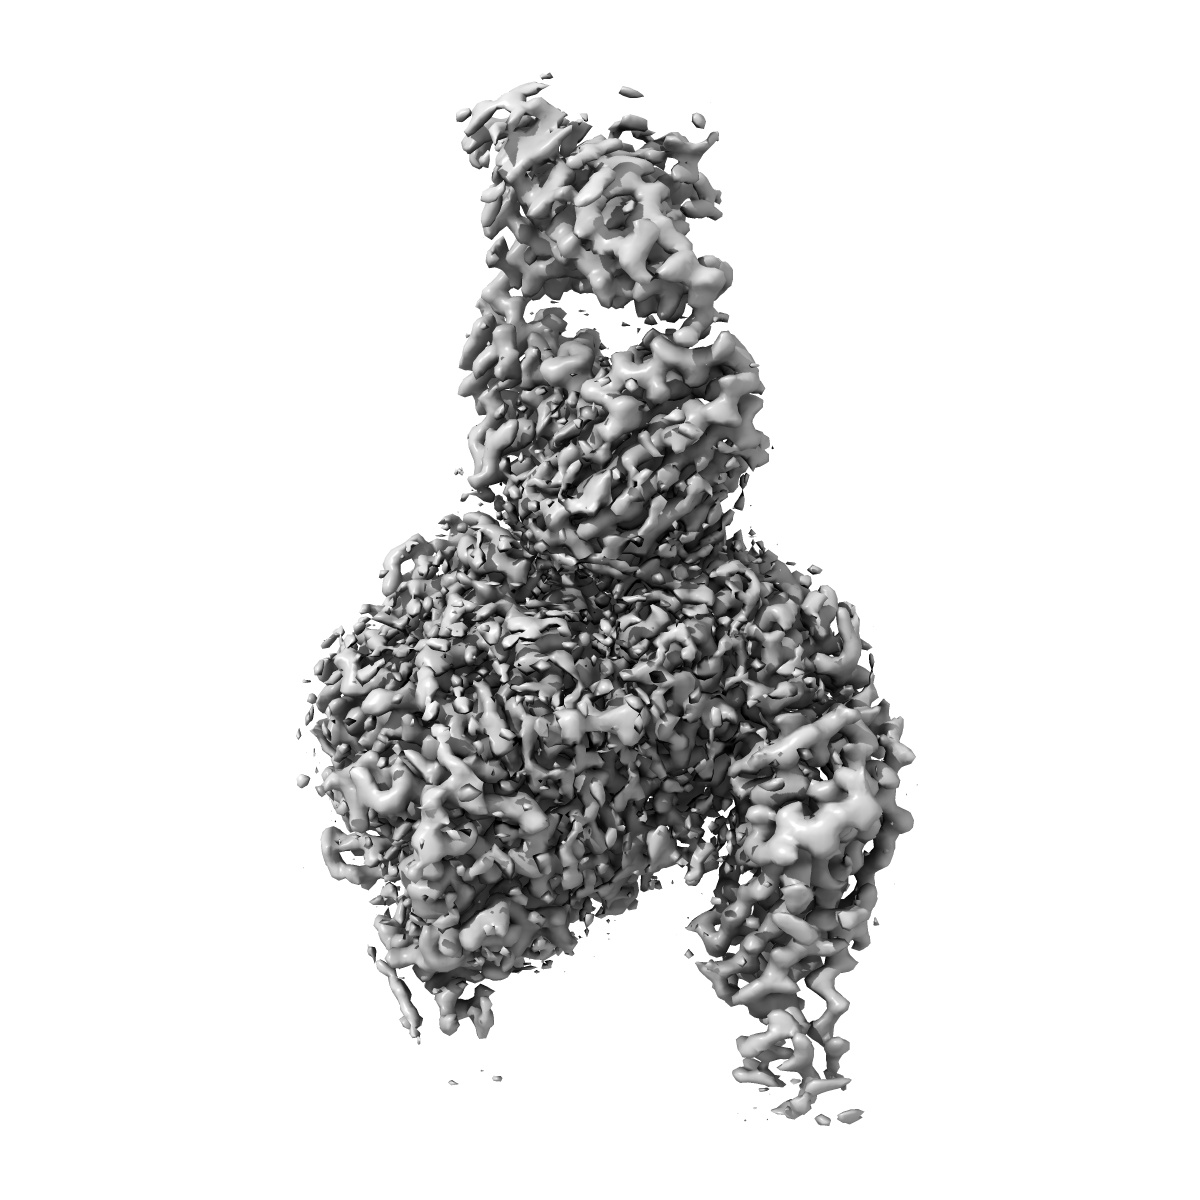

Cryo-EM structure of the integrin AlphaIIbBeta3-Abciximab complex

Cryo-Electron Microscopy Structure of the alpha IIb beta 3-Abciximab Complex.

Nesic D, Zhang Y, Spasic A, Li J, Provasi D, Filizola M, Walz T , Coller BS

(2020) Arterioscler Thromb Vasc Biol , 40 , 624 - 637